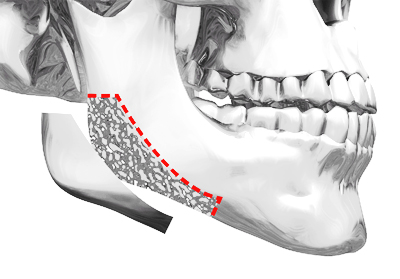

CASE 02 피질골 절제술

CASE 02 피질골 절제술정면에서 볼때 얼굴이

넓어보이는 경우 시행 -

입안 최소절개로 절제 공간 확보 후,

신경선을 피해 턱뼈 절제 -

케이스에 따라

피질제거술/교근축소술 병행 -